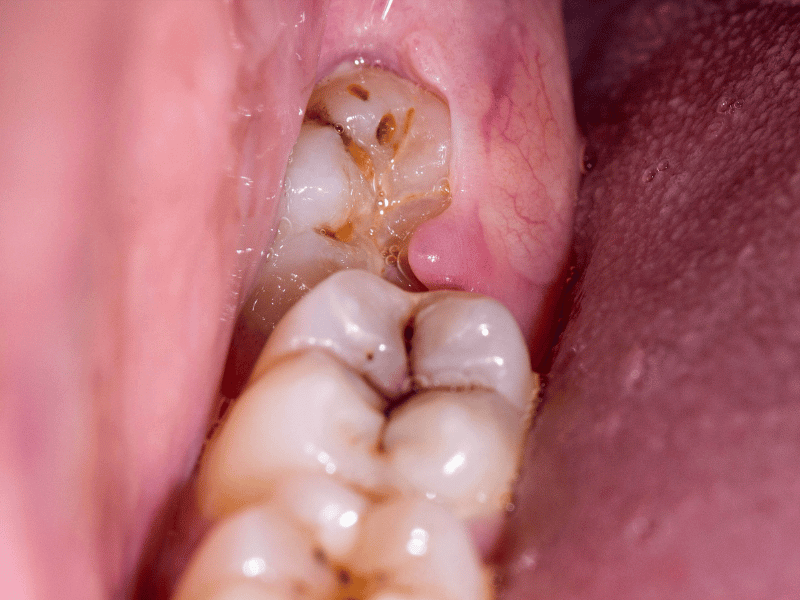

Impacted Lower Left Third Molar

Most often impacted wisdom teeth develop decay and cause a lot of pain necessitating eventual disimpaction. They may also cause decay to develop on the tooth next to it as this area is normally inaccessible. This may necessitate more extensive treatment and sometimes loss of more than one tooth.